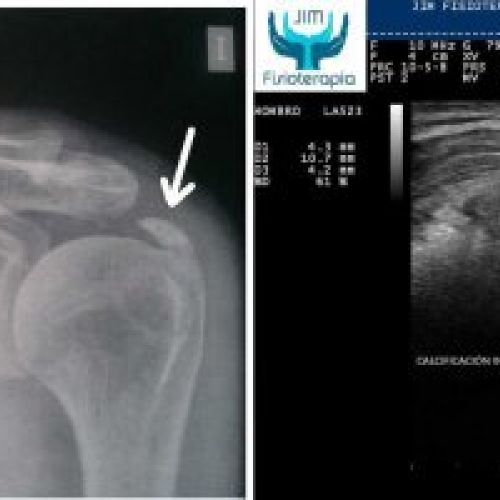

Tratamiento con EPI® de Tendinosis Calcificada del Supraespinoso

Imágenes del tratamiento de un caso de Tendinosis Calcificada del Supraespinoso mediante la terapia EPI® en Madrid.